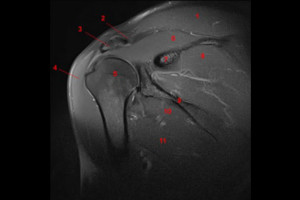

- Reconocer la ecografía normal de las estructuras anatómicas más relevantes del hombro en sus diferentes cortes transversales, longitudinales y según los casos, coronales. Se hará un recordatorio y repaso de la anatomía normal del hombro con especial hincapié en las estructuras articulares, tendinoligamentosas y musculares.

- Aplicación práctica de la ecografía anatómica del hombro y su sistemática exploratoria. Podrá explorar adecuadamente y reconocer el manguito rotador y los diferentes elementos que lo componen (supraespinoso, infraespinoso, subescapular, redondo menor), así como el tendón del bíceps, las diferentes articulaciones que configuran el hombro y otras estructuras (bursas, nervios, ligamentos, etc.).

- Introducir de forma somera al alumno en la patología musculoesquelética, aprendiendo de forma general y sencilla la ecoestructura patológica de las lesiones más frecuentes y relevantes en la práctica clínica.